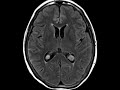

Leptomeningeal Carcinomatosis

There is lack of CSF suppression on FLAIR sequence imaging in scattered cerebral sulci, corresponding to leptomeningeal enhancement. Enhancement is additionally seen along the entire spinal cord and cauda equina. These findings are consistent with leptomeningeal metasases in this patient with a known history of metastatic lung cancer.